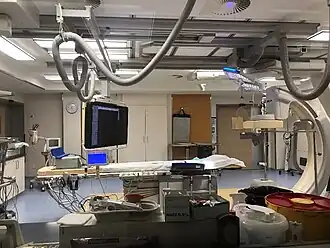

Cardiac catheterization lab | |

A common example of cardiac catheterization is coronary catheterization that involves catheterization of the coronary arteries for coronary artery disease and myocardial infarctions ("heart attacks"). Catheterization is most often performed in special laboratories with fluoroscopy and highly maneuverable tables. These "cath labs" are often equipped with cabinets of catheters, stents, balloons, etc. of various sizes to increase efficiency. Monitors show the fluoroscopy imaging, electrocardiogram (ECG), pressure waves, and more.